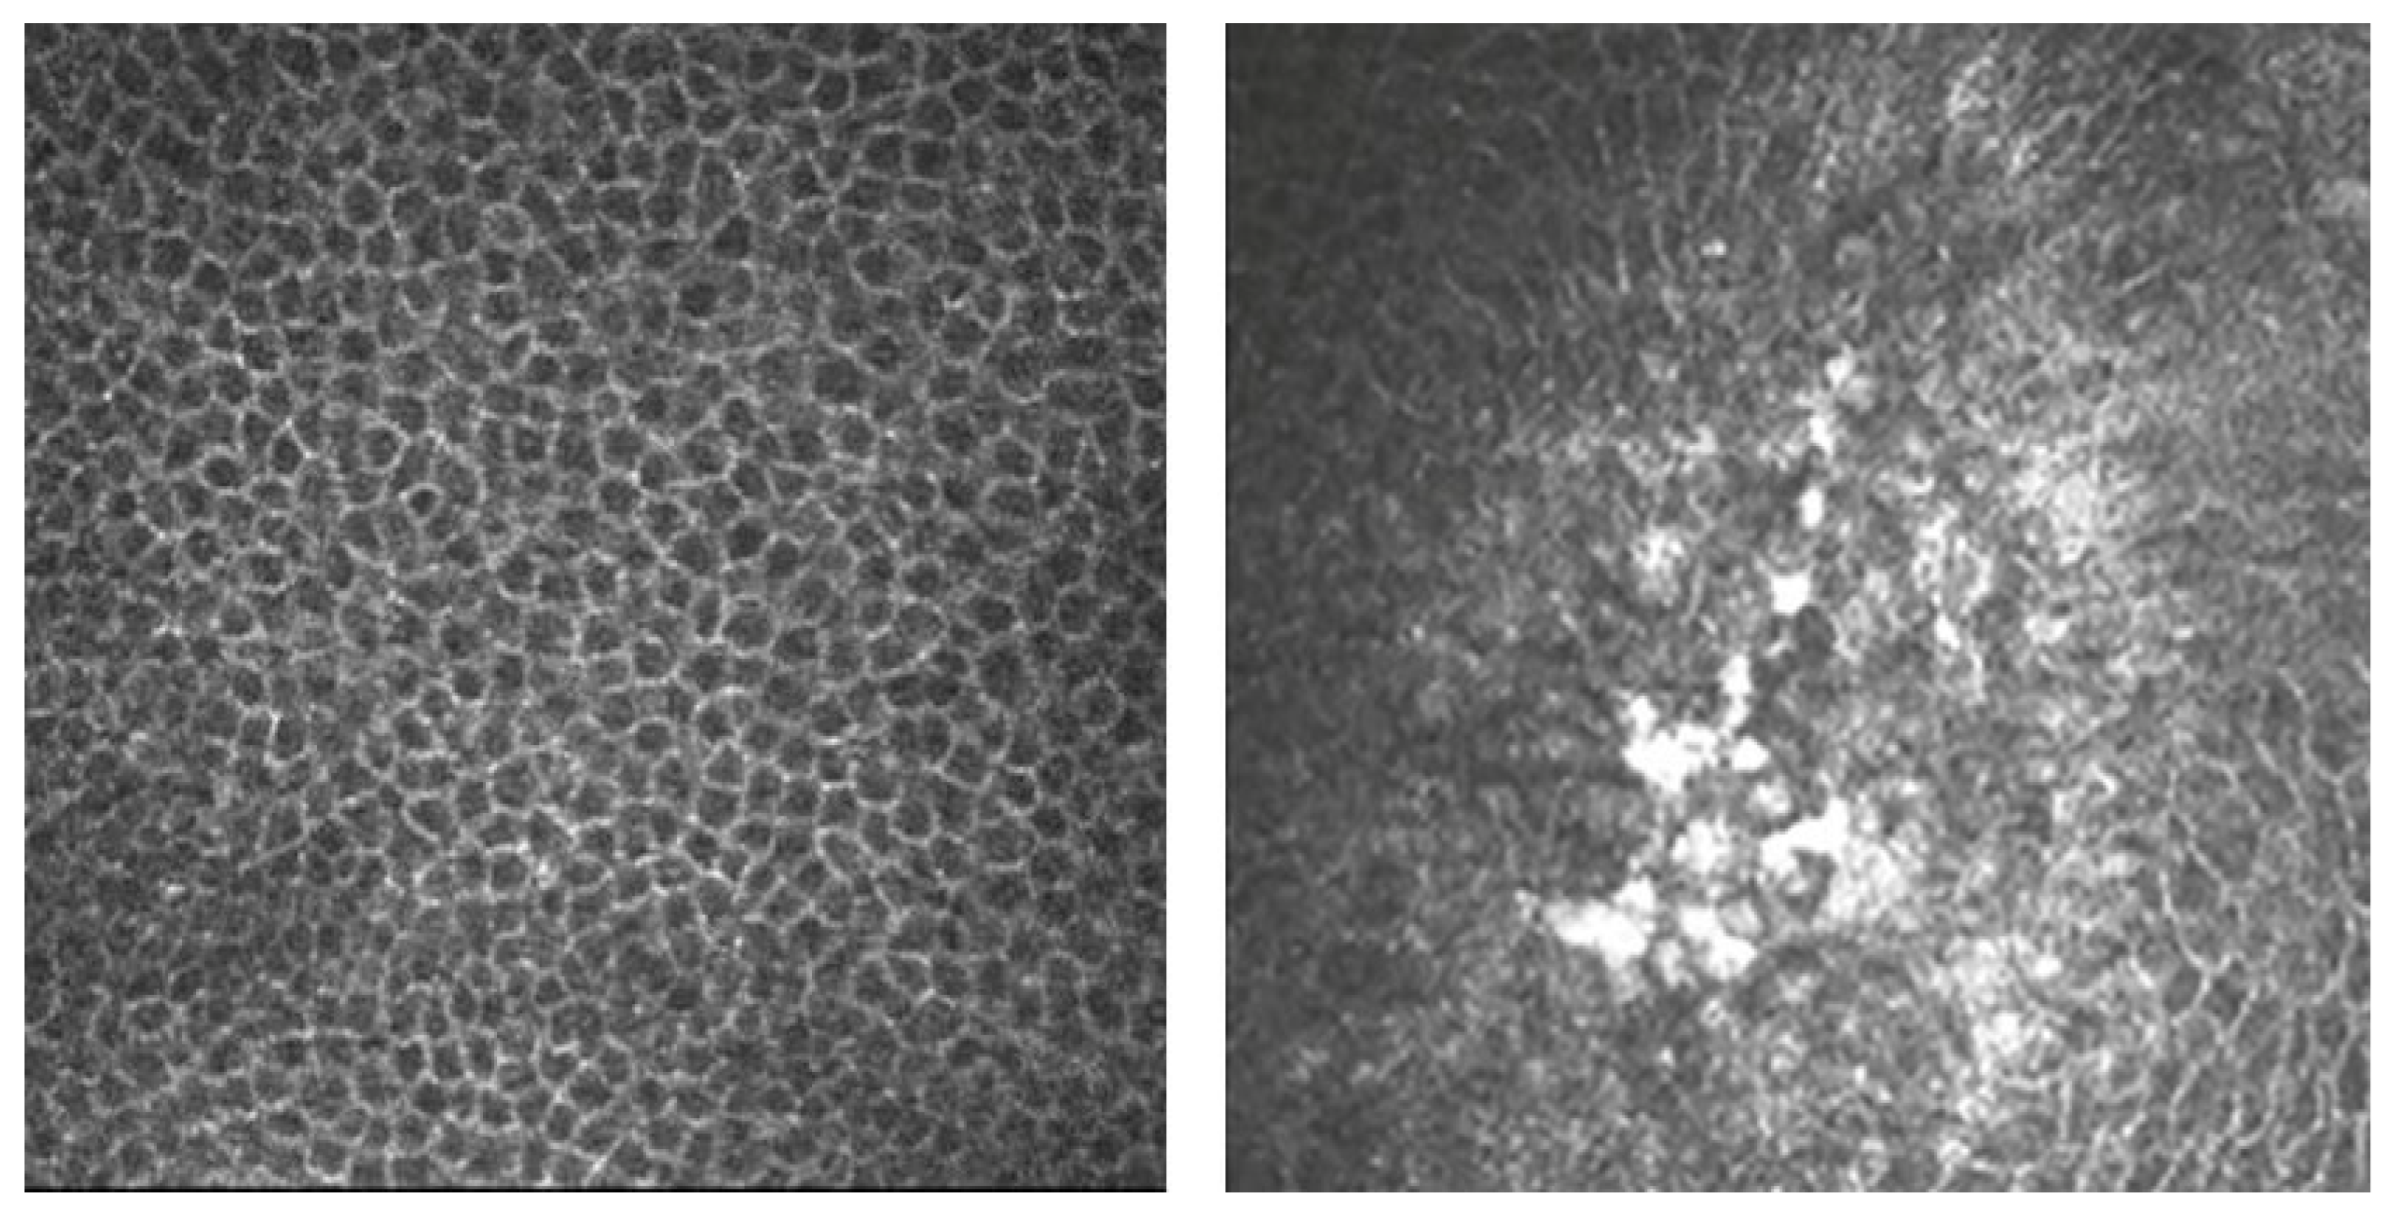

3.6. In Vivo Confocal Microscopy Clinical Applications

- Yokogawa, H.; Kobayashi, A.; Mori, N.; Sugiyama, K. Mapping of Dendritic Lesions in Patients with Herpes Simplex Keratitis Using in Vivo Confocal Microscopy. Clin. Ophthalmol. 2015, 9, 1771–1777. [Google Scholar] [CrossRef]

- Nagasato, D.; Araki-Sasaki, K.; Kojima, T.; Ideta, R.; Dogru, M. Morphological Changes of Corneal Subepithelial Nerve Plexus in Different Types of Herpetic Keratitis. Jpn. J. Ophthalmol. 2011, 55, 444–450. [Google Scholar] [CrossRef]

- Rosenberg, M.E.; Tervo, T.M.T.; Müller, L.J.; Moilanen, J.A.O.; Vesaluoma, M.H. In Vivo Confocal Microscopy after Herpes Keratitis. Cornea 2002, 21, 265–269. [Google Scholar] [CrossRef]

- Mocan, M.C.; Irkec, M.; Mikropoulos, D.G.; Bozkurt, B.; Orhan, M.; Konstas, A.G.P. In Vivo Confocal Microscopic Evaluation of the Inflammatory Response in Non-Epithelial Herpes Simplex Keratitis. Curr. Eye Res. 2012, 37, 1099–1106. [Google Scholar] [CrossRef] [PubMed]

| Yokugawa et al. [57] | 4 | Hyperreflective irregular epithelial cells surrounded by elongated epithelial cells. Langerhans cells within the epithelium and nerve plexus |

| Rosenberg et al. [59] | 10 | Highly reflective dendritic structures in the basal epithelium |

| Mocan et al. [60] | 11 | Infiltration of basal epithelial layers with inflammatory cells |

| 20 | Stromal inflammation evidence: round-shaped, with hyperreflective nuclei, smaller than keratocytes, surrounded by microdeposits | |

| 18 | Keratic precipitates (KPs): in 11 eyes, small round KPs; in 9, globular KPs; in 8, dendritiform KPs | |

| 17 | Endothelial blebs as hyporeflective dark spaces between endothelial cells | |

| 19 | Alteration in the sub-basal plexus: attenuated in 9 eyes, not visible in 10 eyes | |

| Hamrah et al. [62] | 32 | Lower mean nerve density, total nerve number, main nerve trunks, and number of branches |